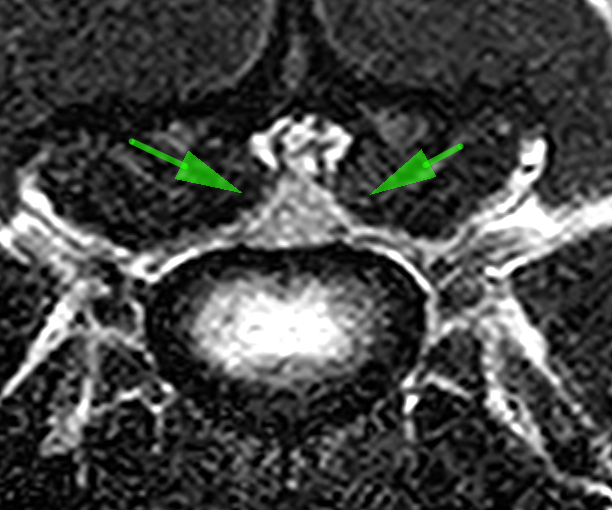

MRI画像検査です。頚椎2−3の圧迫が確認されました。

頚椎3−4での圧迫が確認されました。

椎体中央部の正常な脊髄です。脊髄周囲には脳脊髄液があり、狭窄がないのがわかります。